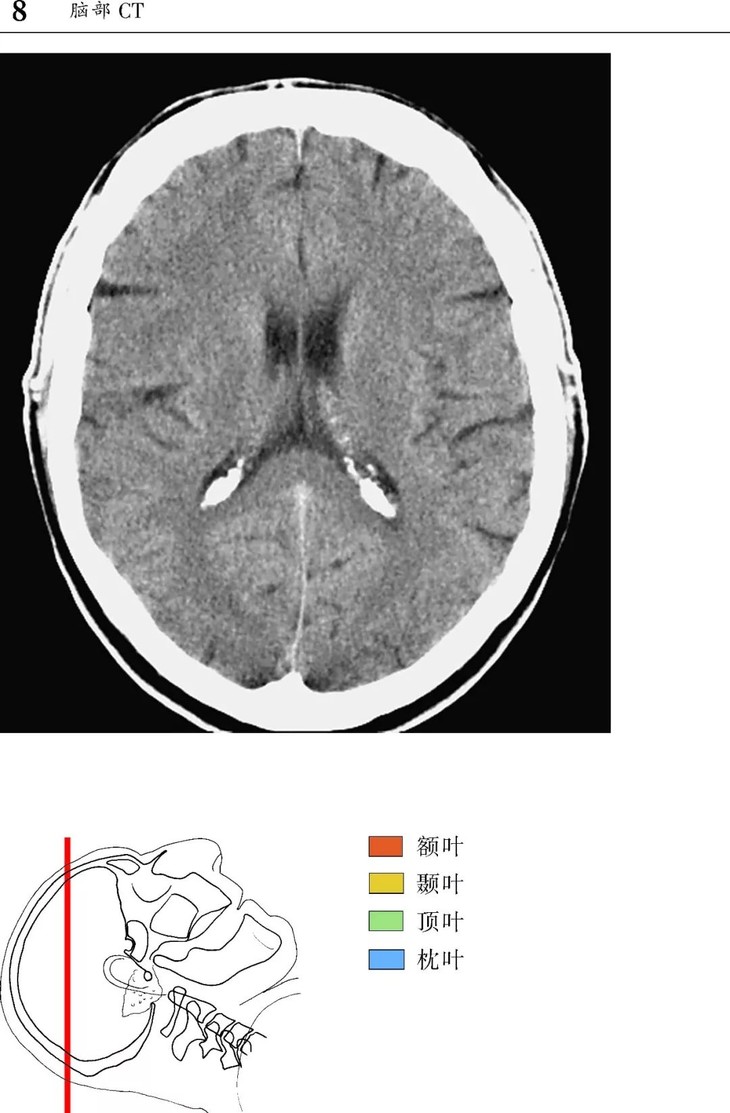

本书为断层解剖图谱,包括头颈部断层解剖,还包括脑部血管造影术,每一层面都包括精确的断层解剖和对应的彩色插图,左边页面为CT/MR图像,右边页面为对应的彩色手绘解剖示意图,便于学习和记忆!

1、版面采用教学式设计,2页为一个单元,左边页面为CT/MR图像,右边页面为对应的彩色手绘解剖示意图,并一一注明了解剖部位。

2、几百幅高清的CT/MR图片,对解剖结构显示更加清晰,其中许多图片都是采用最新的设备扫描的,如3.0T MRI,64层CT。

3、彩色手绘示意图中,各断层图像中同一个解剖结构均采用相同的颜色标注,便于识别。